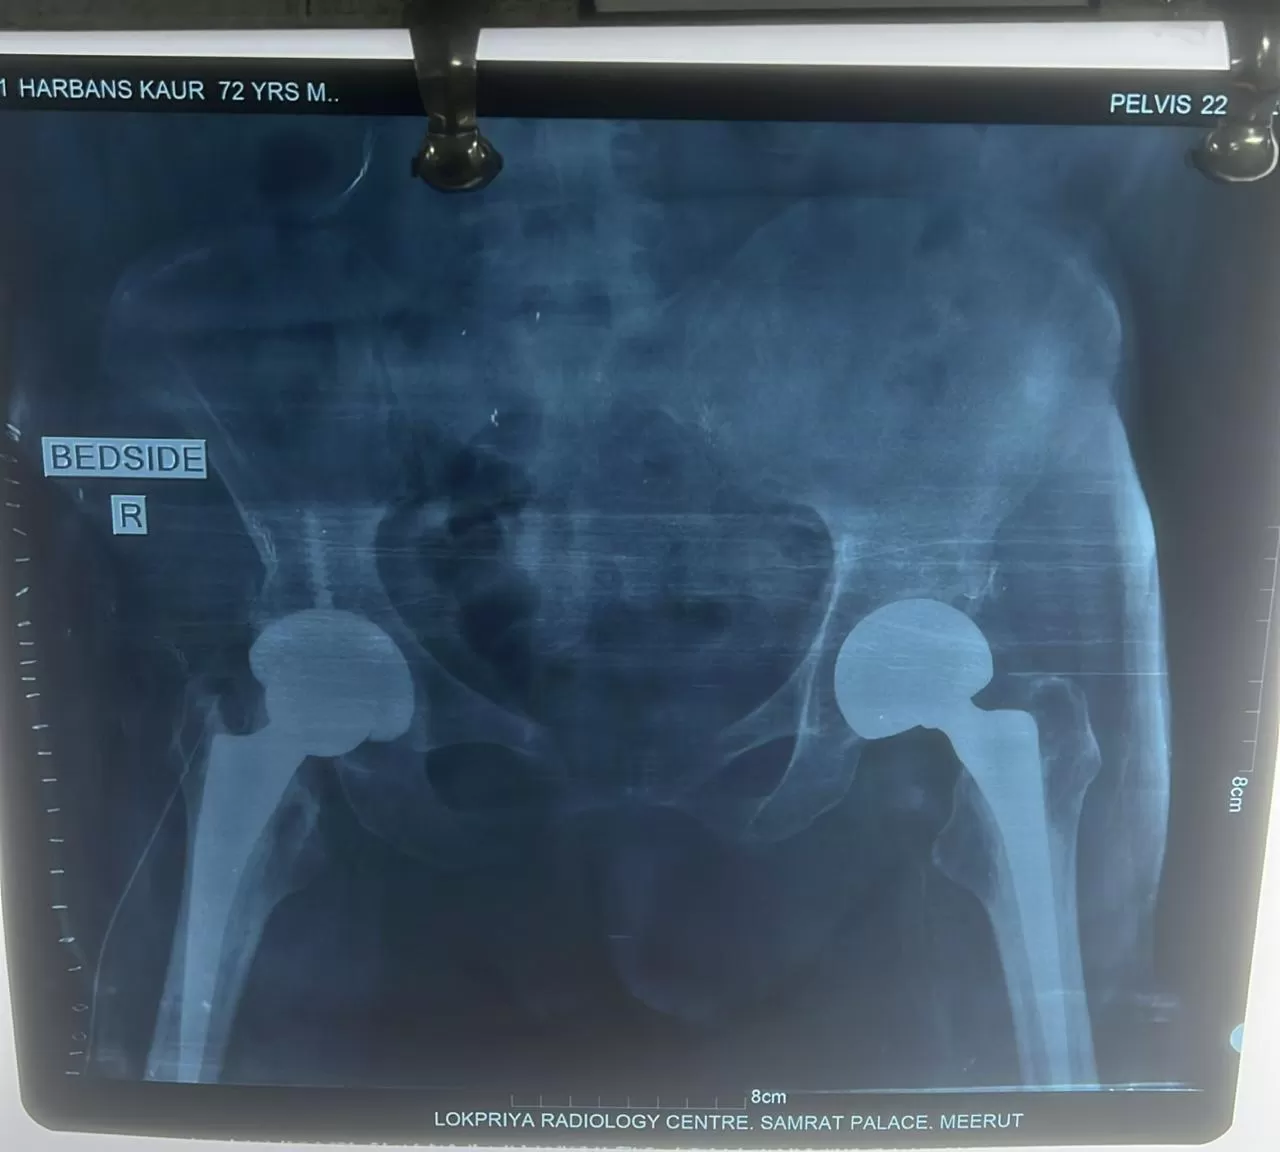

Name: Harbhajan

Date of Operation: 22 October

Age: 70 Years